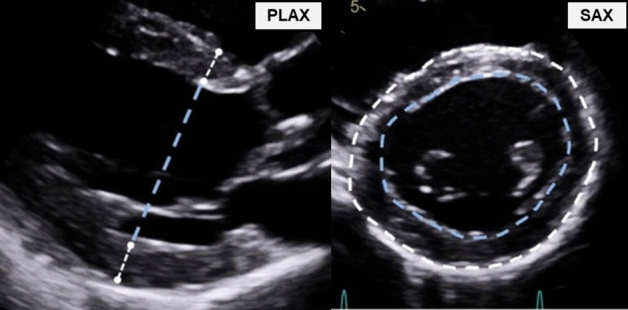

One experienced sonographer performed all examinations at both baseline and re-examination, using a Vivid E95 ultrasound scanner (GE Healthcare, Norway), and M55c-D-matrix-array transducer (1.5–4.6 MHz) for 2DE and a 4 V-D volume-phased array transducer (1.5–4 MHz) for 3DE. Subjects were studied in the left lateral decubitus position with parasternal long-axis view (PLAX), short-axis view (SAX), apical four-chamber view (4CH), apical two-chamber view (2CH), and 3DE. We reduced depth to focus on the LV. Framerate for 2DE was 65 ± 7 frames/s, and for 3DE 26 ± 8 volumes/s. The 3DE full volume dataset was acquired from the apical window during breath-hold over four to six heart beats. The examinations were analysed using EchoPAC version 201.61 (GE Healthcare, Norway). End-diastole was defined as the first frame of mitral valve closure. We distinguished between the end-diastolic-volume (EDV) defined by the inner myocardial interface [endocardium (EDVENDO)] and by the outer myocardial interface [epicardium (EDVEPI)]. Conventional EDV (EDVENDO) was quantified by 3DE, 2DE using the biplane model9 and 1DE using the Teichholtz model10. LVM-quantifications were made at end-diastole. ECG-timing from PLAX was referenced to find the corresponding SAX-frame. All PLAX/SAX-measurements were made at the chordae level (Fig. 1). In PLAX the region between the mitral valve and papillary muscle, just beneath the attachment of the chordae to the papillary muscle. In SAX this corresponded to the visible attachments of the chordae to the papillary muscle. In this view, the mitral valve should not be visible, and chordae should be separated from LV wall. We delineated the boundaries in SAX by using the blood-endocardium interface, the inner boundary delineation and by the epicardium-blood/pericardium interface, outer boundary delineation. We didn’t use a leading-to-leading edge approach. Trabeculae or papillary muscles were considered part of the LV cavity, the pericardium was excluded from the delineation. 3DE LVM was quantified by the vendor-specific software package 4D Auto LVQ (EchoPAC, GE Healthcare, Norway). The full volume dataset was aligned for three apical views, which were manually adjusted, guided by the derived short-axis views.

Figure 1.

Wall thickness measurements at the chordae level. PLAX parasternal long-axis, SAX parasternal short-axis.